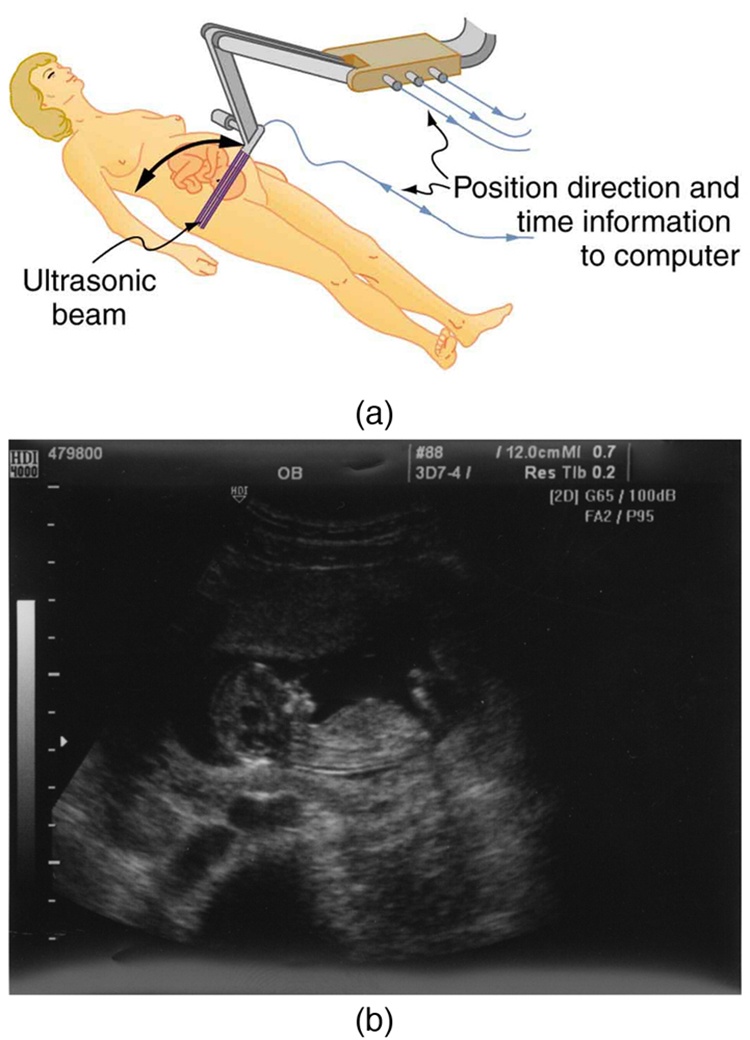

The most common ultrasound applications produce an image like that shown in this figure. The speaker-microphone broadcasts a directional beam, sweeping the beam across the area of interest. This is accomplished by having multiple ultrasound sources in the probe’s head, which are phased to interfere constructively in a given, adjustable direction. Echoes are measured as a function of position as well as depth. A computer constructs an image that reveals the shape and density of internal structures.

How much detail can ultrasound reveal? The image in this figure is typical of low-cost systems, but that in this figure shows the remarkable detail possible with more advanced systems, including 3D imaging. Ultrasound today is commonly used in prenatal care. Such imaging can be used to see if the fetus is developing at a normal rate, and help in the determination of serious problems early in the pregnancy. Ultrasound is also in wide use to image the chambers of the heart and the flow of blood within the beating heart, using the Doppler effect (echocardiology).